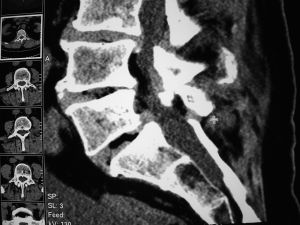

CT gesteuerte Schmerztherapie an der Wirbelsäule

Man unterscheidet 3 Verfahren der CT gesteuerten Infiltrationen

- Facettengelenksinfiltartionen:Die Wirbelbogengelenke werden bei degenerativen oder pseudoradikulären Schmerzen,welche einen Bandscheibenvorfall vortäuschen können infiltriert.

- Wurzelinfiltartionen:Wird hauptsächlich eingesetzt bei seitlichen Bandscheibenvorfällen

- Epiduralinfiltartionen:Hiermit werden die übrigen Bandscheibenvorfälle behandelt, das heißt, es wird eine Nadel genau zu dem Bandscheibenvorfall eingebracht.

Bei diesem Verfahren wird eine oder mehrere Nadeln an den Entstehungsort der Schmerzen eingebracht und anschließend ein Gemisch aus Cortison,Lokalanästhetikum und einem Schmerzmittel appliziert. Im Anschluss daran liegt der Patient bei Wurzel oder Epiduralinfiltrationen bis zu 45 Minuten .